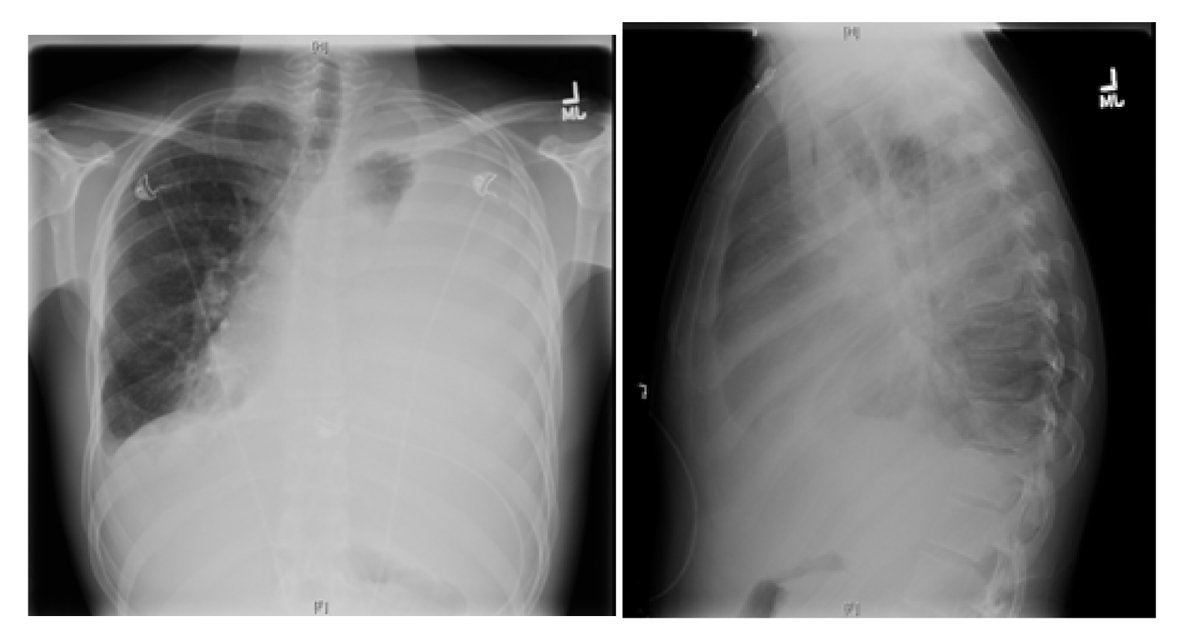

Further work-up revealed a normal complete blood count and comprehensive metabolic panel. X-ray chest showed almost complete opacification of the left lung due to large pleural effusion, and shift of mediastinum toward right due to the effusion (Fig. 1).

![]() Click for large image | Figure 1. X-ray chest showing near complete opacification of left lung due to massive pleural effusion with shift of mediastinum to right. |